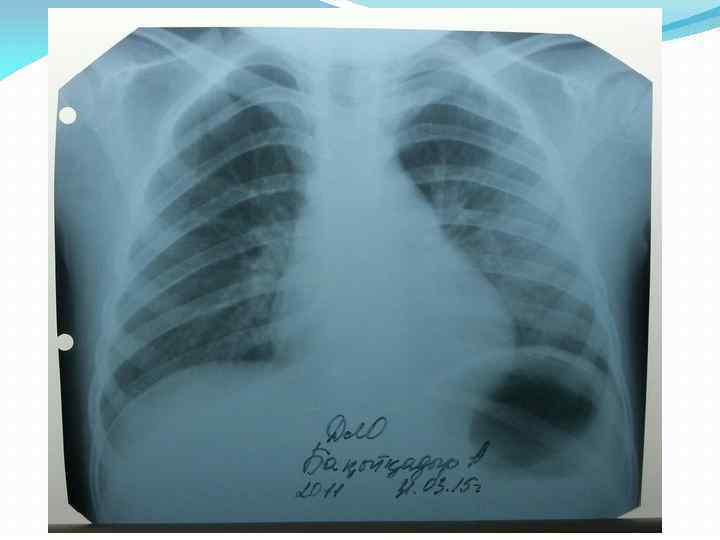

R-графия грудной клетки от 26. 03. 15 г. Заключение: легочные поля с обоих сторон прозрачные. Корни легких справа - структурные, слева - в области тела в головке корня отмечается дополнительное образование, обусловленные увеличенными лимфоузлами. R-графия грудной клетки от 31. 03. 15 г. Заключение: легочные поля прозрачные. Легочный рисунок усилен в прикорневой зоне, больше слева. Корни легких структурные , слева – головка корня инфильтрированное. Верхнедолевой бронх слева завуалирован. Синусы свободные. Тень средостения не изменена. Справа – границы в пределах возрастой нормы.